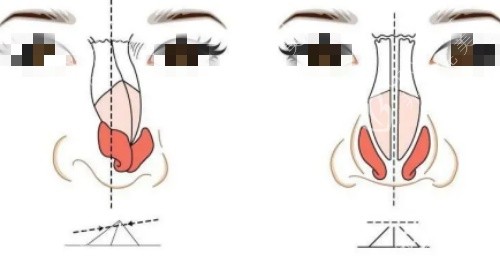

张医生拿个小探头在我鼻梁上扫了扫,说:“你这是假体层次放浅了才透光,鼻头歪是因为缝合时固定点没对齐,不用重做假体,把假体往深了调,再重新固定鼻头就行,还能保留你之前的鼻型基础,修复更快。”没有夸大结果,全是实实在在的分析。